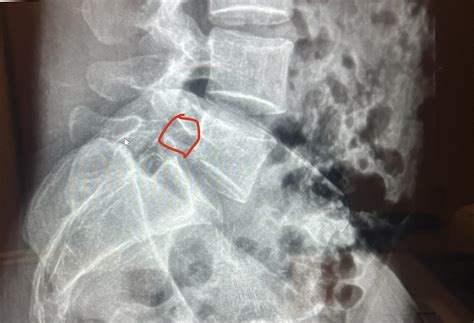

Diagnosing Spondylolisthesis Grade 1

Diagnosing Spondylolisthesis Grade 1 involves a combination of medical history, physical examination, and imaging tests. The diagnostic process typically includes:

• Imaging Tests: X-rays, CT scans, and MRI scans are commonly used to visualize the spine and determine the degree of slippage.

Imaging tests are particularly important for confirming the diagnosis and assessing the severity of the condition. X-rays can show the alignment of the vertebrae, while CT scans and MRI scans provide detailed images of the soft tissues and nerves.